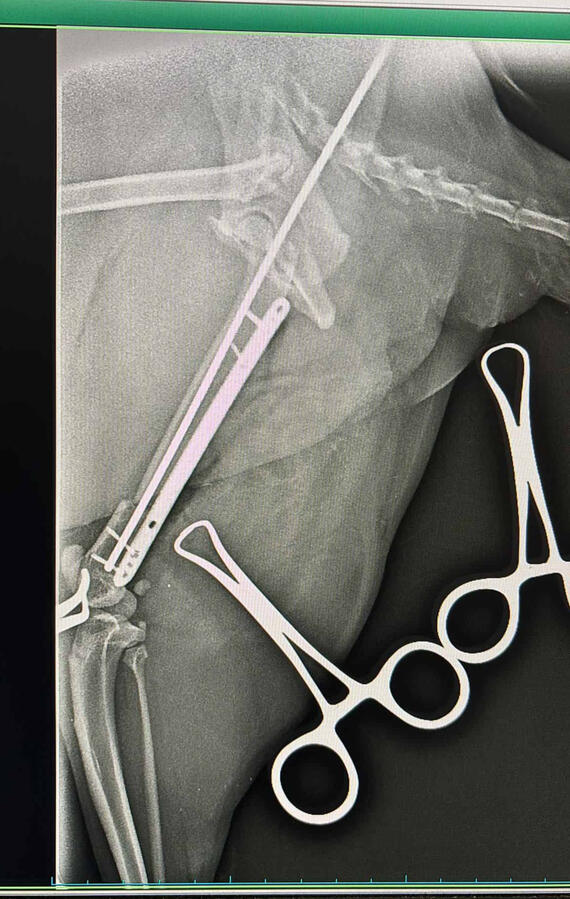

In addition, I continuously train in the areas of orthopedics, traumatology, and pain control. General and traumatological surgery.